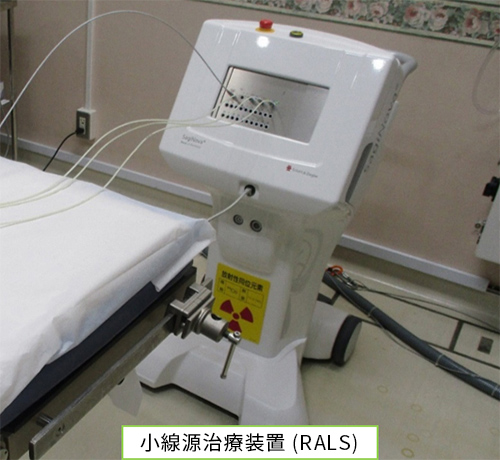

密封小線源治療

密封小線源治療には、腔内照射、組織内照射があります。主に、子宮頸がんや前立腺がんなどで行われています。 腔内照射では、小線源治療装置 (RALS) を使用します。子宮などの腔内にあらかじめ細い管を挿入し、その管を通して放射線源を送り込むことで治療します。